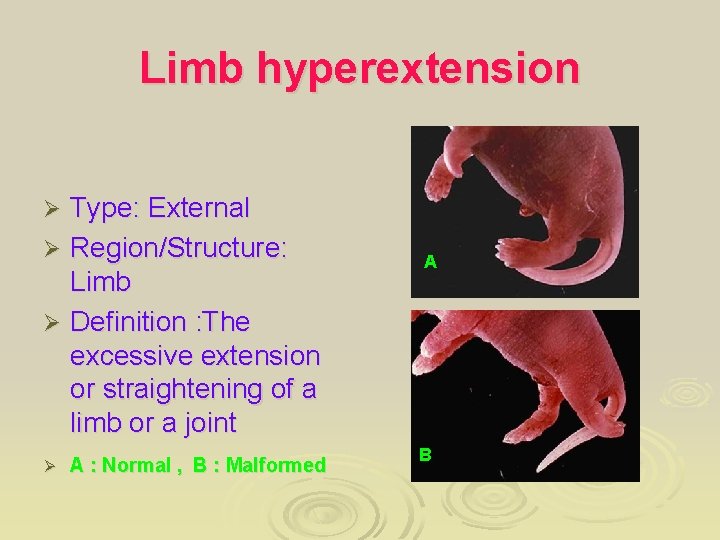

Limb hyperextension Type: External Ø Region/Structure: Limb Ø Definition : The excessive extension or straightening of a limb or a joint Ø Ø A : Normal , B : Malformed A B